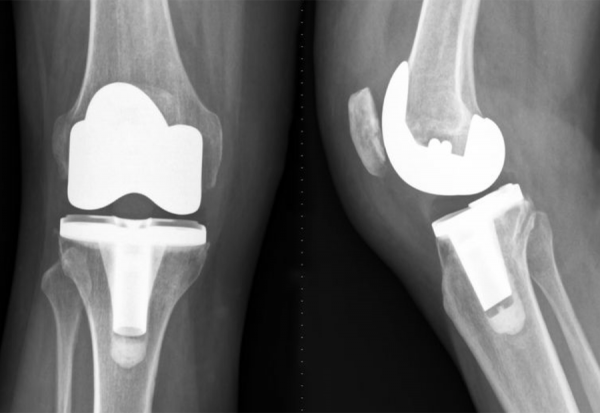

Η ολική αρθροπλαστική γόνατος είναι μια από τις πιο διαδεδομένες & αποτελεσματικές επεμβάσεις στην ορθοπεδική χειρουργική. Αποτελεί τη λύση για άτομα που υποφέρουν από έντονο πόνο & περιορισμένη κινητικότητα λόγω οστεοαρθρίτιδας κά

Οι αρθροπλαστικές ισχίου και γόνατος είναι από τις πιο επιτυχημένες επεμβάσεις στην ορθοπεδική, προσφέροντας ανακούφιση από τον πόνο και βελτίωση της κινητικότητας. Ωστόσο, υπάρχουν περιπτώσεις..κά